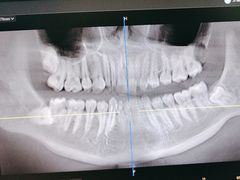

• 牙博士口腔品牌连锁(杨浦店)

• -牙博士口腔品牌连锁(杨浦店)